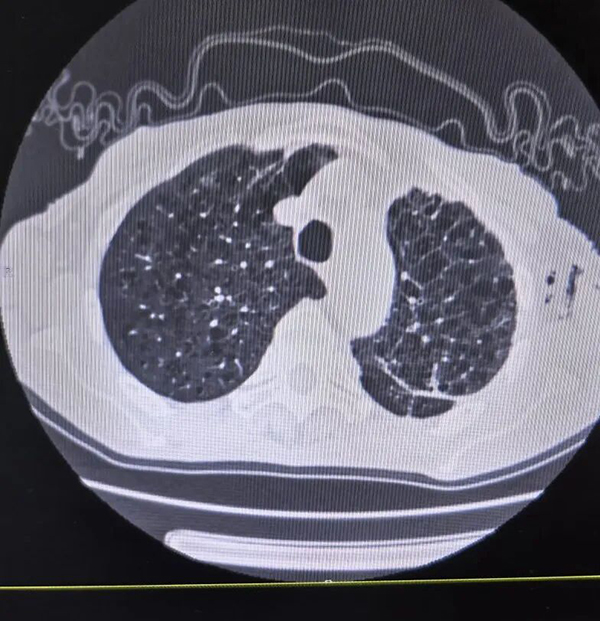

近日复查显示:瘘口完全愈合,肺部复张良好。出院前,团队经气管镜将“完成使命”的封堵海绵取出,那根陪伴了李老伯数月的引流管也终于被拔除。李老伯激动地说道:“太感谢你们了,这下终于可以把管子甩掉了!”

(复查CT显示肺部复张良好,完成使命的海绵被取出)